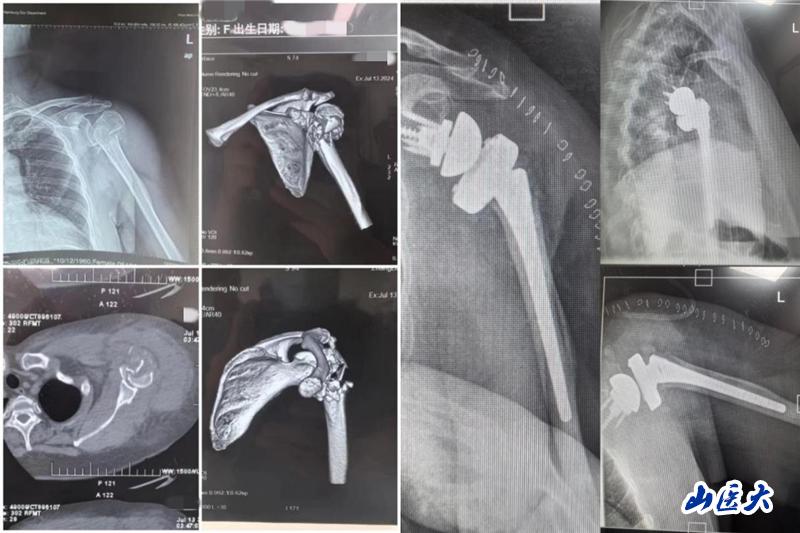

患者是一位63岁女性,主因车祸致左肩关节疼痛、肿胀伴活动受限就诊,完善相关检查结果示:左肱骨近端粉碎性骨折。栗树伟副主任医师团队多次进行术前病例讨论,综合患者年龄较大、骨折类型为严重肱骨近端粉碎性骨折、肩关节功能严重受损等因素考虑,本着最大程度提高患者生活质量的医疗服务理念,决定为患者实施反向肩关节置换术。

术后的精心护理对患者的恢复也至关重要,护理团队耐心、细心、用心地护理和交流让患者充分感受到关爱与温暖。目前,患者术后拍片假体安置满意,切口愈合佳,肩关节功能恢复良好,现已顺利出院。